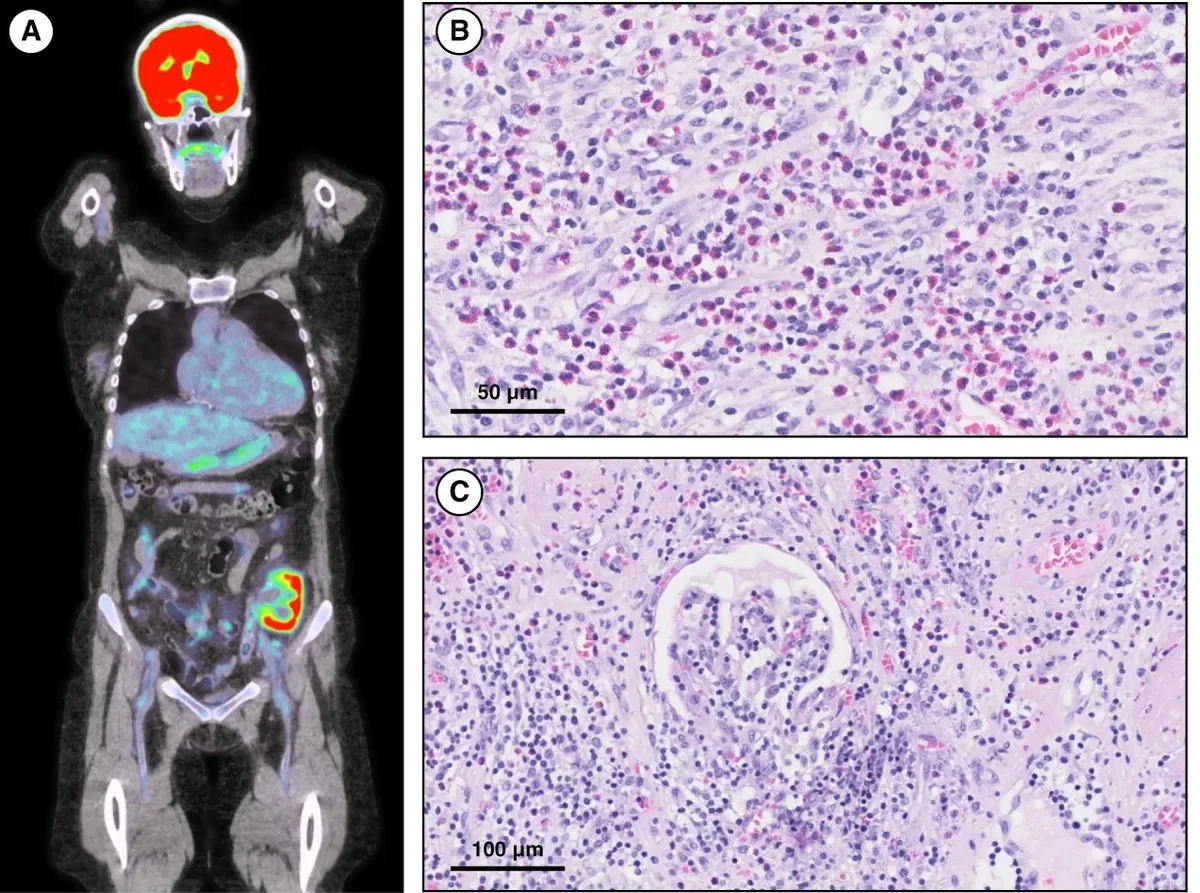

IRA + Icterícia: Um Caso que Exige Investigação Detalhada